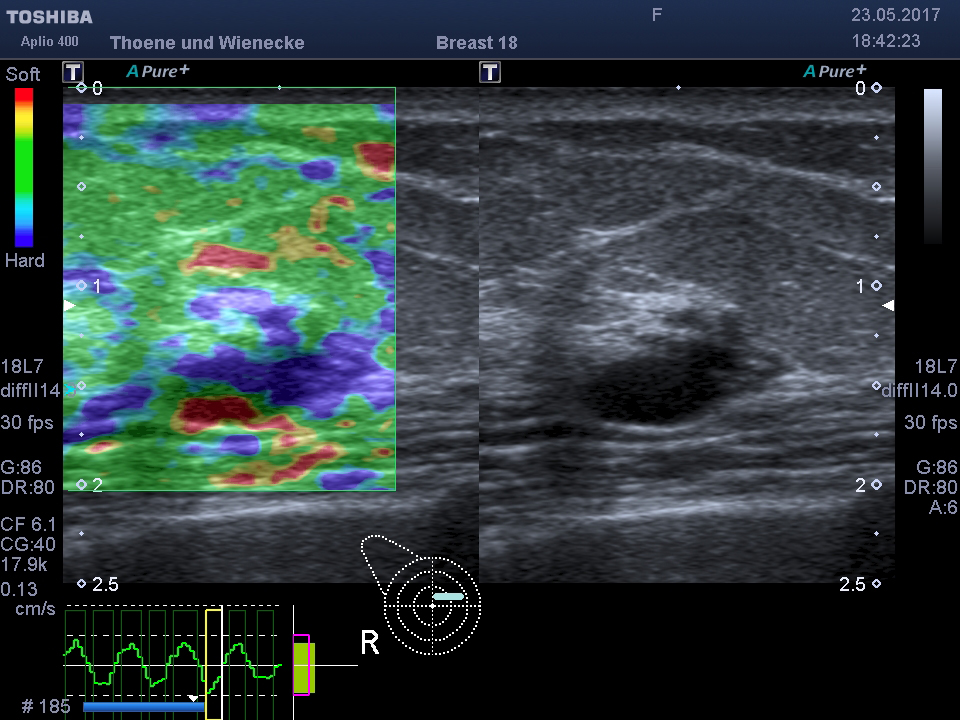

Elastographie der Brust

3D Sonographie der Brustdrüse

Was ist der Unterschied zur normalen Sonographie?

Der Ultraschall ist eine Untersuchung ohne Strahlenbelastung. In unsrer Praxis werden hochauflösende Ultraschallköpfe verwendet, die eine hohe Genauigkeit und sehr gute Auflösung ermöglichen. D.h. auch kleinste Veranderungen können schon gesehen werden. Mit der 3 D Sonographie können Veränderungen des Gewebes in ihrer Abgrenzung zum normalen umgebenden Gewebe besser beurteilt werden als nur mit der 2 D Methode. Bösartige Knoten bilden Ausläufer in das umgebende Gewebe, die wie kleine Strahlen einwachsen. Diese Phämomene können mit der 3 D Sonographie beurteilt werden, die Unterscheidung zwischen gutartigen und bösartigen Veränderungen wird genauer und die Rate an unnötigen Biopsien kann vermindert werden.